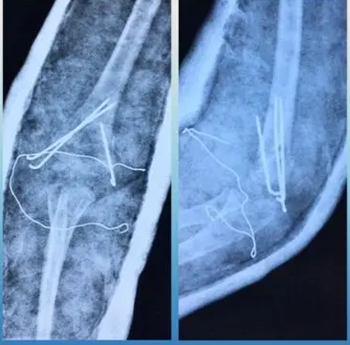

病例一:患儿女,7岁,摔伤

图 3 术后骨折完美复位